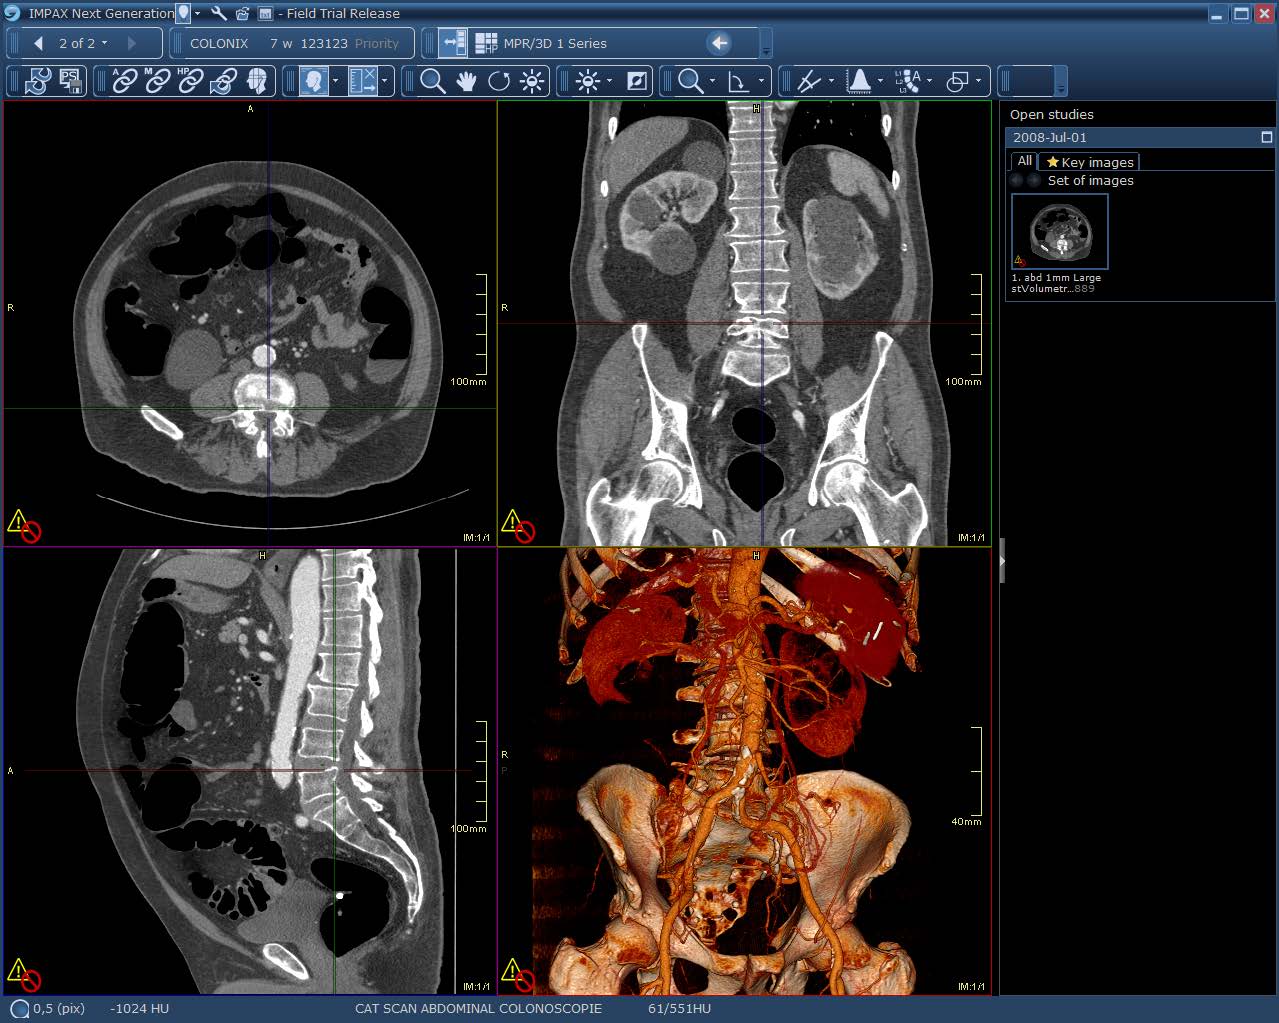

Volumetric imaging is widely used in medicine and life sciences allowing to gain insight into otherwise opaque objects. Volumetric images do not unveil their content in a direct way due to their spatial structure. Therefore a variety of computational methods are used for visualization and processing which allow to explore and analyze the data.

Analysis and exploration of the data is usually performed in an interactive way either manually or with support of semi-automatic algorithms. It is crucial for an efficient completion of the task that the system performs interactively and responsively. Thus, software supporting the user in an effective way relies on three basic requirements. First, the system must deliver feedback in a short period of time. Second, results of any computation must be presented or visualized in a way that the user can efficiently recognize the important information. Third, the user must be able to efficiently control, initialize or adjust the algorithm through a suitable user interface. In this thesis four approaches are presented which aim to solve different aspects of the problem of enabling interactivity in analysis and exploration of volumetric image data.